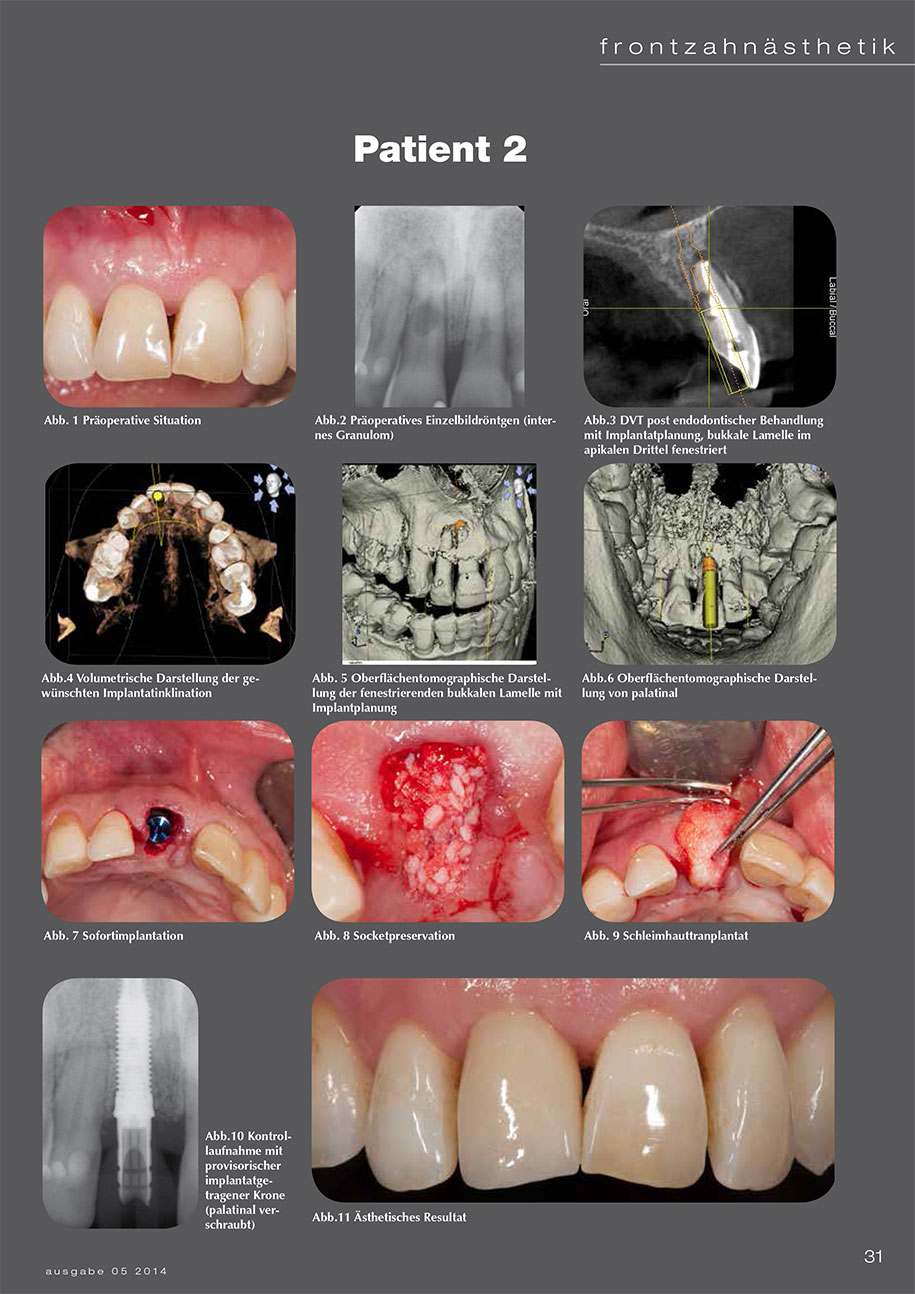

4 Patientenbeispiele